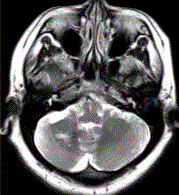

问题 患者女,41岁。头痛半年,加重10d。头部MRI显示如下图。 根据该病的影像学表现,该病可能的诊断是

选项 A.海绵状血管瘤 B.发育性静脉畸形 C.AVM D.毛细血管扩张症 E.动脉瘤 F.硬脑膜动静脉瘘

答案 AB